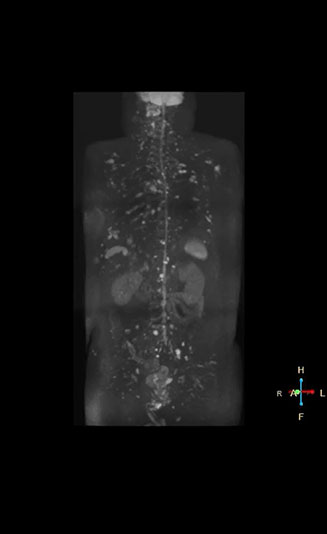

Kawasaki Sawai Hospital’s whole body protocol also includes an mDIXON FFE sequence. Because mDIXON provides images for four contrast types – water only, fat only, in-phase and out-of-phase – from a single acquisition, it is useful in many ways.

“mDIXON FFE allows us to quickly get information we need to assess the presence of fat. That gives us more information when we need to diagnose bone lesions, and when we are asked to judge fat-containing lesions such as hepatocellular or renal carcinoma,” Dr. Nobusawa says.

“The mDIXON fat images can help us to differentiate fatty bone marrow from bone lesions. This is especially useful in elderly people, who tend to have fattier bone marrow. The water images provide a high signal-to-noise ratio in the intestinal canal, which is valuable for visualizing lesions in the colon,” he says.

“In-phase and out-phase sagittal T1-weighted FFE images help us to visualize and further characterize bone lesions such as metastasis and bone-marrow hyperplasia that have high signal on DWI. These images are also used throughout radiotherapy, to monitor changes in the fatty bone marrow.”